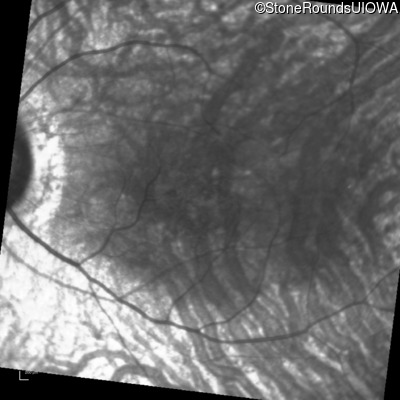

Infrared Fundus Photograph - Right - 20/40

Exemplar